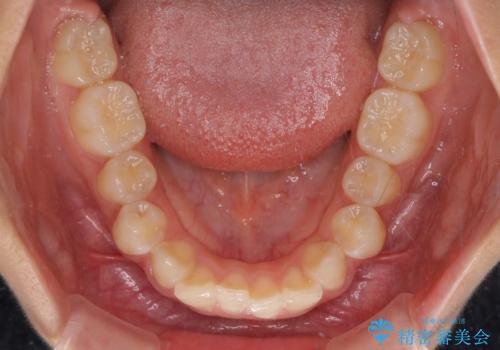

深い咬み合わせで前方に煽られた前歯 高校生のインビザライン矯正治療

- 前歯の隙間と前方に飛び出していることを気にして来院された患者様です。

奥歯の咬み合わせを見ると、上顎が下顎に対して相対的に前方にありました。

咬み合わせも深くなっていたため、上顎臼歯を後方に移動させつつ、下顎の小臼歯を直立させ、奥歯の咬み合わせを改善する必要があります。

インビザライン単体で対応することも検討できますが、達成する可能性が低いため、カリエールディスタライザーという補助装置を併用して、より確実性を上げることとしました。

奥歯の咬み合わせと深い咬み合わせを改善した後、隙間などをインビザラインで整えることとしました。